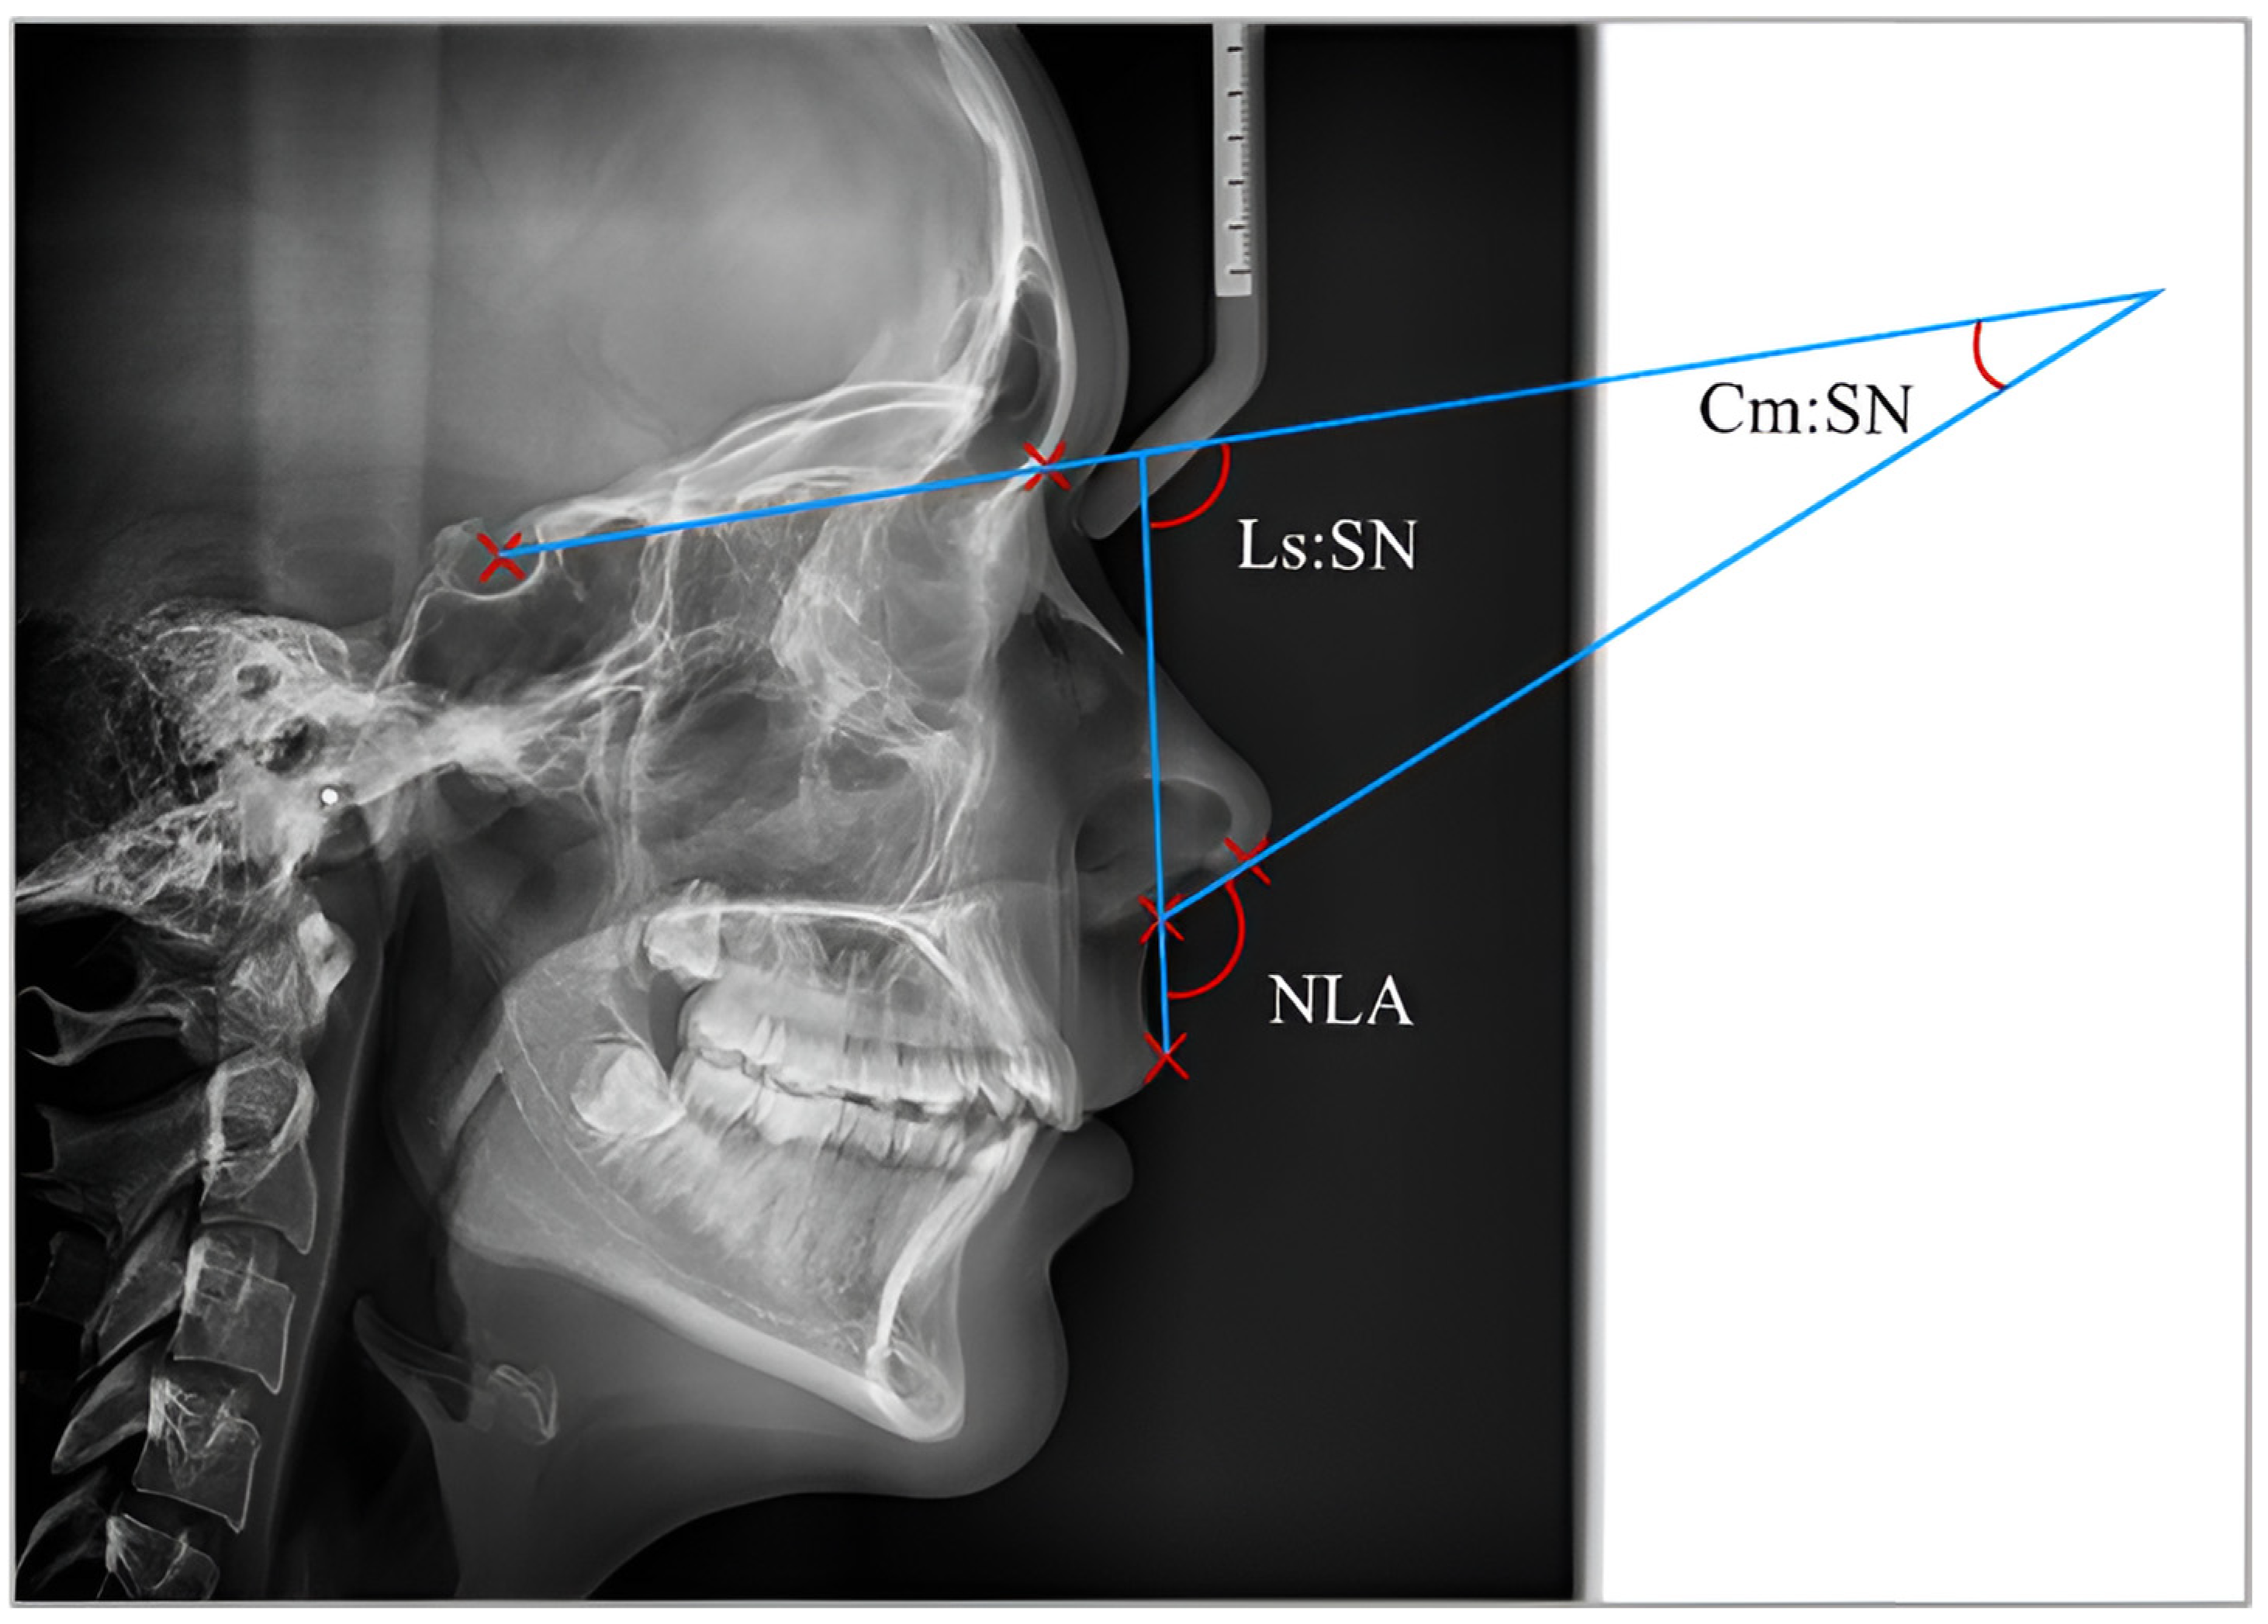

| Columella nasi—Cm | The external end of the nasal septum. |

| Labral superior—Ls | The uppermost point of the upper lip. |

| Subnasale—Sn | A sagittal point where the nasal septum and the upper lip meet in the midsagittal plane. |